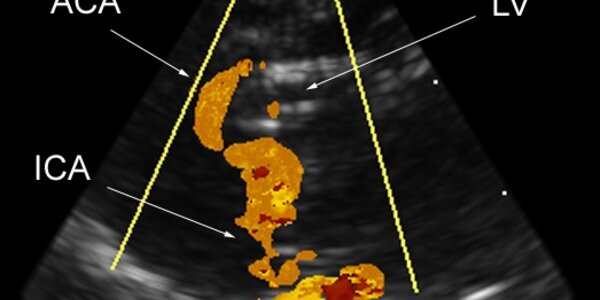

The Brain Scope - Seeing The Brain In 3-D

Biomedical engineers at Duke's Pratt School of Engineering have adapted a three-dimensional ultrasound scanner that might guide minimally invasive brain surgeries and provide better detection of a brain tumor’s location. The “brain scope,” which is inserted into a dime-sized hole in the skull, may be particularly useful for the bedside evaluation of critically ill patients when computed tomography (CT) and magnetic resonance imaging (MRI) equipment is unavailable, the researchers said. Brain surgeons now rely primarily on two-dimensional images produced by MRI or ultrasound, said Edward…